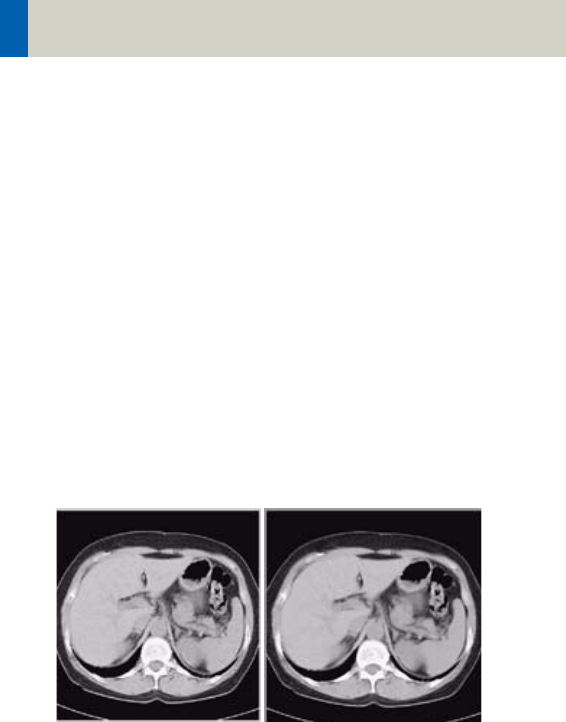

LCE: The Low-contrast enhancement filter enhances

low-contrast detectability. It reduces the image noise.

• Similar to reconstruction with a smoother kernel

• Reduces noise

• Enhances low-contrast detectability

• Adjustable in four steps

• Automatic post-processing

Image taken without

the LCE filter

Image taken with the LCE

filter